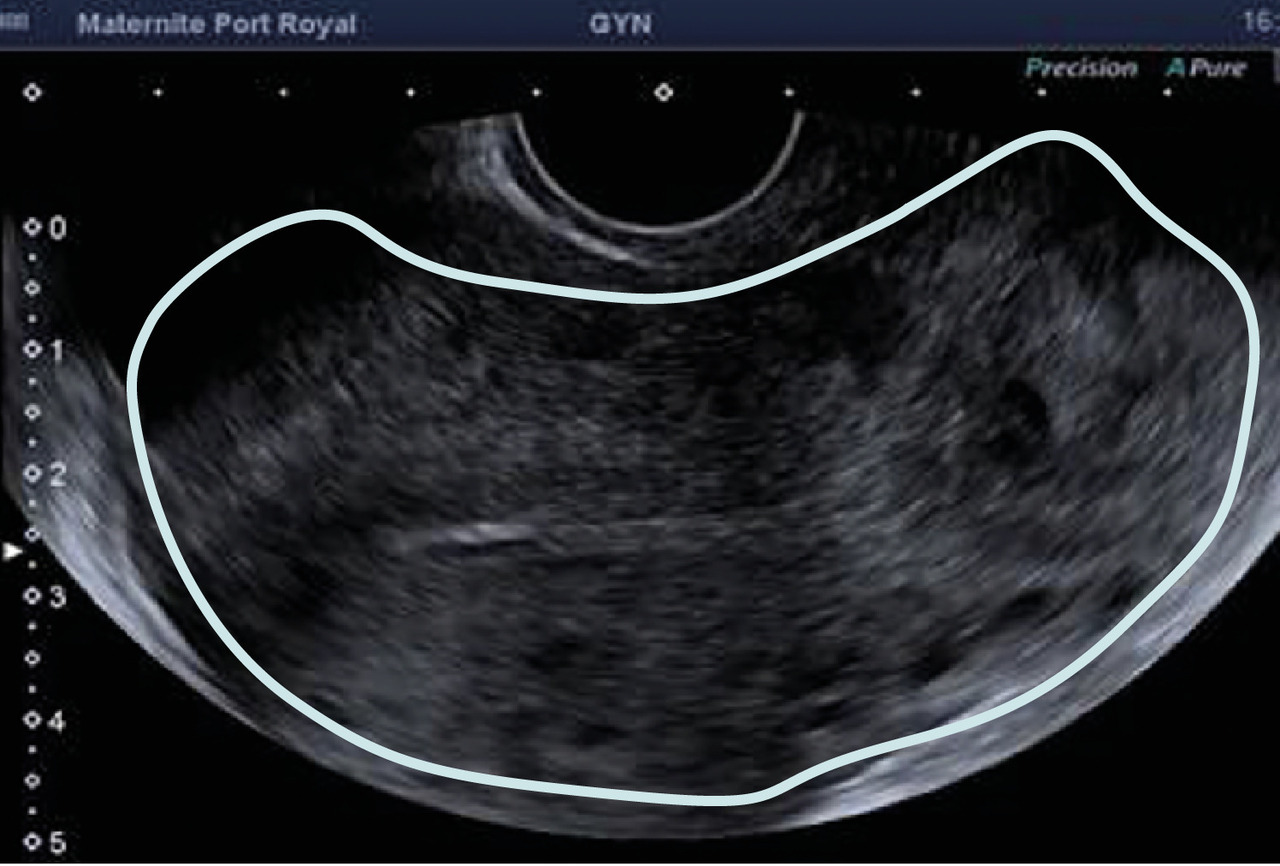

L’échographie, indispensable, doit examiner le pelvis mais aussi l’abdomen. Elle est donc réalisée par voie endovaginale, sus-pubienne et abdominale. On peut visualiser une masse latéro-utérine (fig. 1). Au sein de cet hématosalpinx, un sac gestationnel peut être visible, voire un embryon (fig. 2) ayant parfois une activité cardiaque positive. Le passage de la sonde à ce niveau est douloureux.

Souvent, le principal signe est indirect :

– vacuité utérine (fig. 3) et taux de hCG supérieur à 1 500 UI/L, fortement évocateurs. En cas de métrorragies, une lame d’hématométrie peut être visible en intra-utérin (« pseudo-sac gestationnel » : image hypo-échogène centrée dans la cavité, sans couronne trophoblastique) ;

– épanchement abdomino-pelvien, traduisant un hémopéritoine. Il est visible en échographie pelvienne dans le cul-de-sac de Douglas et en écho abdominale dans l’espace de Morrison (situé entre le foie et le rein droit ; dans ce cas, évoquer une GEU rompue avec hémopéritoine important).